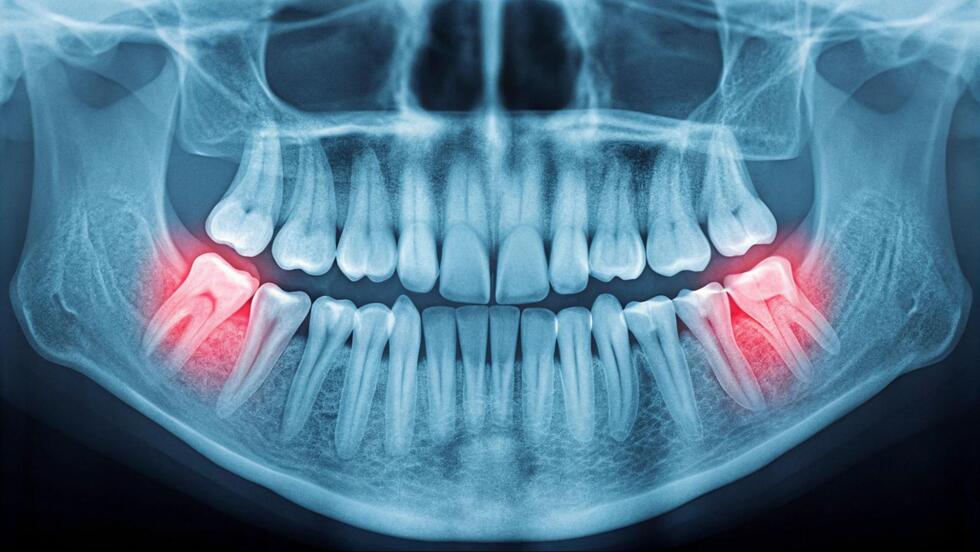

親知らずに違和感を覚えたり、一番奥の奥歯が痛んだりしていませんか?親知らずは歯ブラシが届きにくい場所にあるため、虫歯になりやすく、気づいた時にはかなり進行していることも少なくありません。「まだ大丈夫」と思っているうちに、隣の歯まで虫歯が広がってしまうケースもあります。

親知らずは一番奥にあるため歯ブラシの毛先が届きにくく、どんなに丁寧に歯磨きをしても、磨き残しが多くなる傾向にあります。また、現代人は顎が小さくなっている傾向があり、親知らずが生えるスペースが不足していることも多いです。そのため、親知らずが斜めや横向きに生えてしまうこともあり、隣の歯との間に深い溝ができやすくなります。

親知らずの虫歯を放置すると、隣接する第二大臼歯にも虫歯が広がる可能性があります。親知らずと隣の歯の間に汚れがたまりやすい環境ができているため、虫歯菌が繁殖しやすくなるのです。第二大臼歯は食べ物を噛み砕く重要な役割をもつ大切な歯です。この歯が虫歯になると、食事の際に痛みを感じたり、しっかり噛めなくなったりして、日常生活に支障をきたします。

初回の受診では、問診とレントゲン撮影を行い、親知らずがどのような向きで生えているか、根の形はどうなっているか、神経との位置関係はどうかなどを詳しく調べます。神経との位置関係を調べる場合は、CTによる検査が必要です。親知らずの痛みや歯茎の腫れがある場合は、虫歯の治療前に炎症を抑える治療が行われます。炎症がある状態では麻酔が効きにくく、抜歯後の治りも悪くなるためです。

時には、隣の歯の虫歯や顎関節の問題が原因で、親知らず付近に痛みを感じることもあります。親知らずと隣の歯の間に食べ物が詰まることで痛みを感じることもあるでしょう。痛みの原因を特定するためには、歯科医院での詳しい検査が必要です。レントゲン撮影や触診、打診検査(歯を叩いて異常がないかを調べる検査)などを通じて、診断と治療を受けることができます。